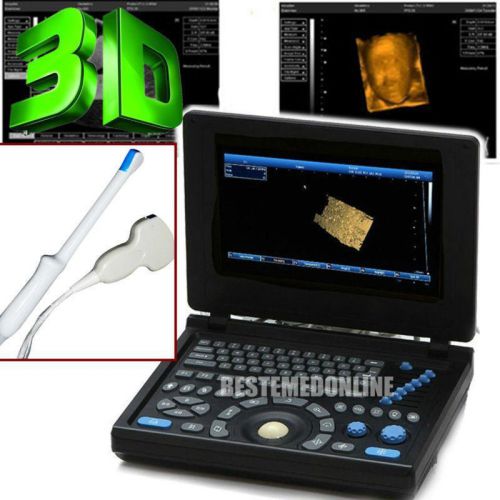

3D Portable Digital Ultrasound Scanner system Micro-Convex Linear Probe

3D PC Based Full Digital Build in 3D Ultrasound Scanner + Linear probe FDA CE

3D Portable Ultrasound Scanner machine system Convex+Linear USB FDA CE

PC Platform Digital Laptop Ultrasound Scanner Convex + TV 2 Probes FDA CE PASS